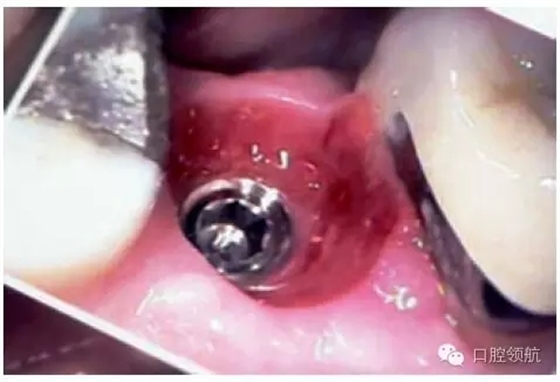

圖9.25 (a)臨床檢查可見(jiàn)軟組織過(guò)厚、基臺(tái)過(guò)短、固位不佳,因此牙冠反復(fù)脫落。(b)臨床檢查可見(jiàn),穿出牙齦的基臺(tái)高度足夠,可以滿(mǎn)足粘結(jié)固位的要求。

另外一個(gè)方面,深的袖口將妨礙修復(fù)體完全就位(圖9.26)。通??梢酝ㄟ^(guò)放射學(xué)檢查,確認(rèn)修復(fù)部件的就位情況,包括種植體與基臺(tái)的連接部分。即使是內(nèi)連接,轉(zhuǎn)移體或者其他修復(fù)部件也會(huì)因深袖口而不能就位。以下技術(shù)可以用于解決這些問(wèn)題:可以在局部麻醉下,插入喇叭狀或者外展的基臺(tái),以非手術(shù)的方式擴(kuò)大袖口(圖9.27 a,b),然后再通過(guò)放射學(xué)檢查確定部件的完全就位。組織會(huì)受壓發(fā)白,15分鐘后,軟組織將會(huì)擴(kuò)張,以允許理想修復(fù)部件的就位,這樣治療將得以繼續(xù)。有時(shí),需要在鄰面做兩個(gè)小切口,以緩解袖口軟組織張力(圖9.28 a,b)。通常不需要縫合。一旦袖口組織塑形完成,可運(yùn)用最佳塑形的臨時(shí)(圖9.29)或最終部件(圖9.30),來(lái)維持理想的軟組織外形。